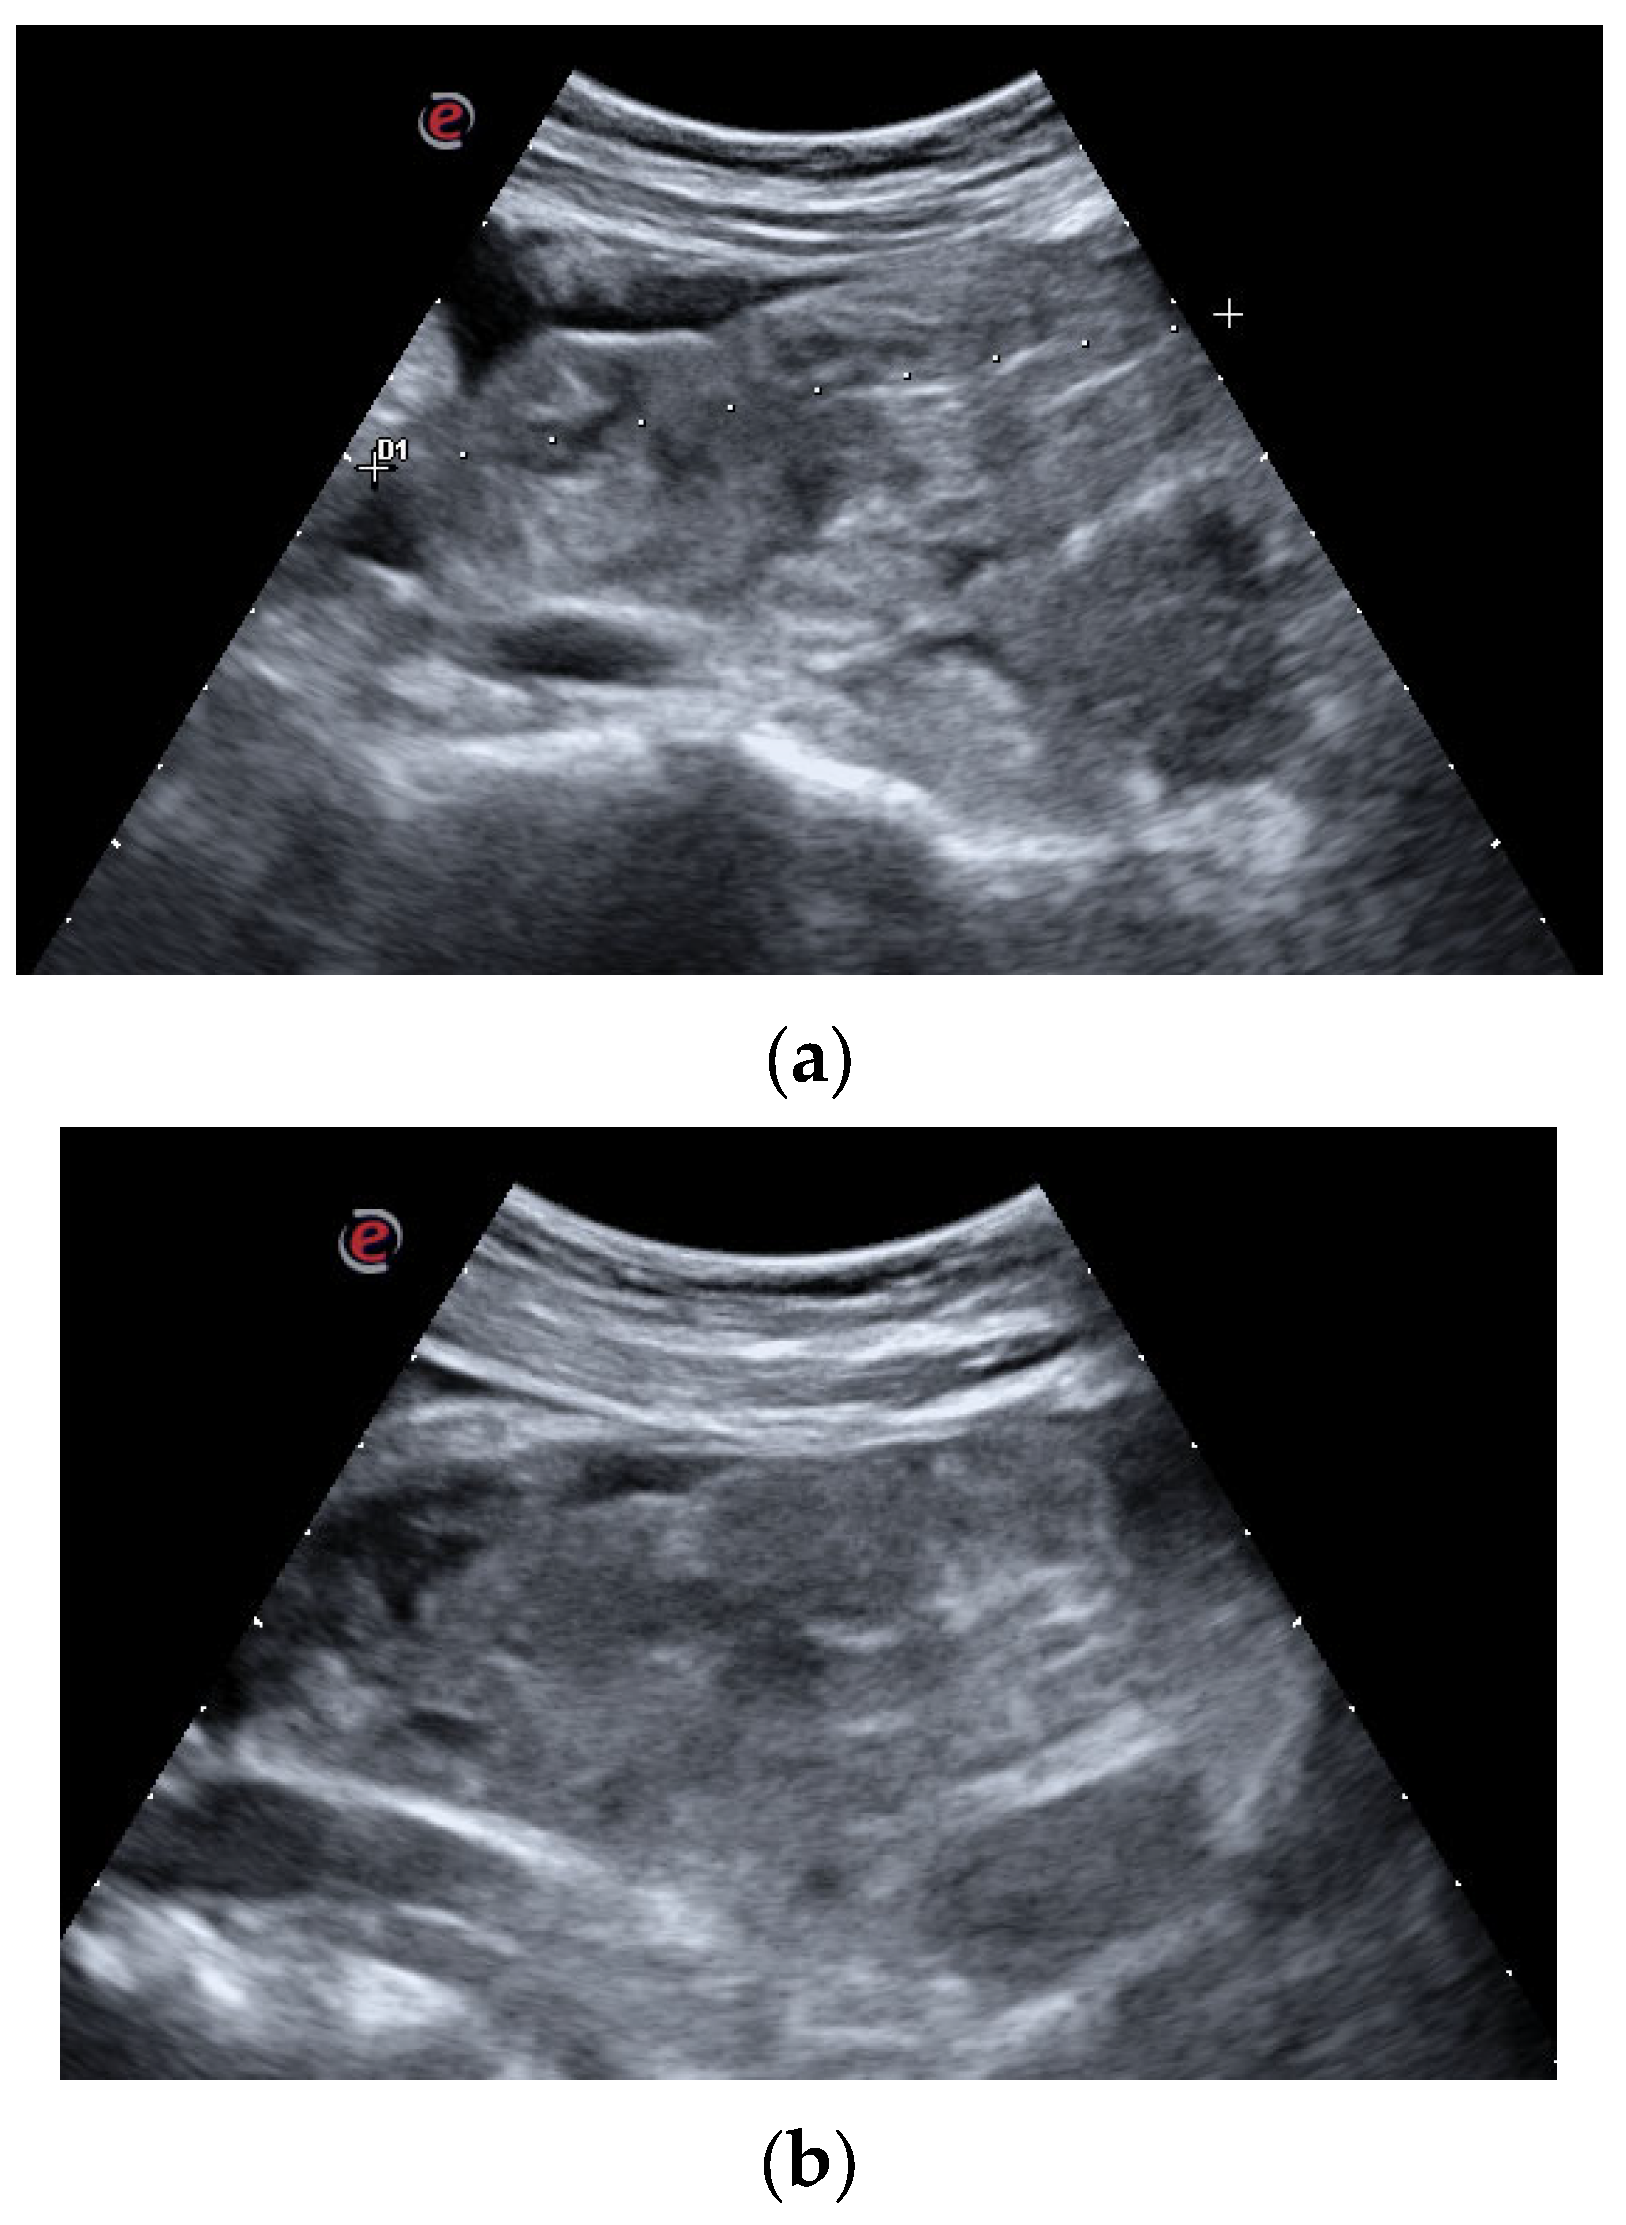

Abdominal US showed a large clot filling the bladder, varying in position depending on the patient decubitus. The clot had a 10 cm diameter as a main projection (Figure 1a,b).

(a,b). Diagnostic Assessment: US images of the large clot occupying the entire bladder lumen. The complex organization and the tight adhesion of its major components are clearly appreciable both in the sagittal scan (a) and in the transversal scan (b).